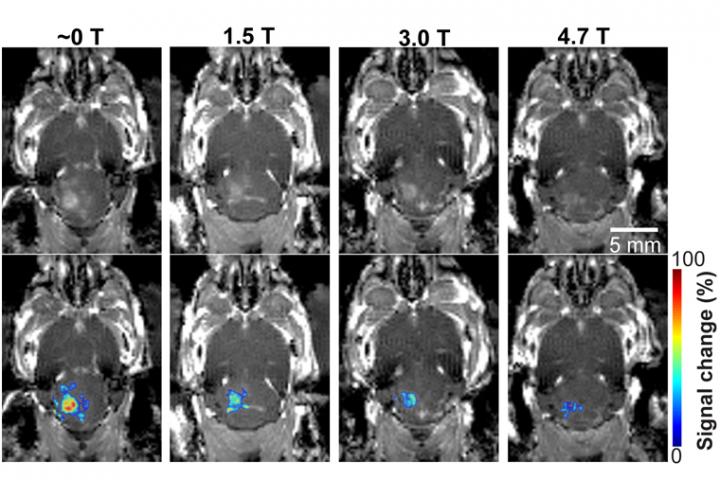

image: In a mouse model study of MRI-guided focused ultrasound-induced blood-brain barrier (BBB) opening at MRI field strengths ranging from ­approximately 0 T (outside the magnetic field) to 4.7 T, the static magnetic field dampened the detected microbubble cavitation signal and decreased the BBB opening volume.

They found that the activity of the microbubble cavitation, or the expansion, contraction and collapse of the microbubbles, decreased by 2.1 decibels at 1.5 T; 2.9 decibels at 3 T; and 3 decibels at 4.7 T, compared with those that had received the dose outside of the magnetic field. In addition, the magnetic field decreased the BBB opening volume by 3.3-fold at 1.5 T; 4.4-fold at 3 T; and 11.7-fold at 4.7 T. None of the mice showed any tissue damage from the procedure.

Following focused-ultrasound sonication, the team injected a model drug, Evans blue, to test whether the static magnetic field affects trans-BBB drug delivery efficiency. The images showed that the fluorescence intensity of the Evans blue was lower in mice that received the treatment in one of the three strengths of magnetic fields compared with mice treated outside the magnetic field. The Evans blue trans-BBB delivery was decreased by 1.4-fold at1.5 T, 1.6-fold at 3.0 T and 1.9-fold at 4.7 T when compared with those treated outside of the magnetic field.